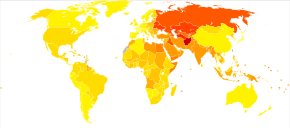

In 2013 CAD was the most common cause of death globally, resulting in 8.14 million deaths (16.8%) up from 5.74 million deaths (12%) in 1990.[6] The risk of death from CAD for a given age has decreased between 1980 and 2010 especially in developed countries.[19] The number of cases of CAD for a given age has also decreased between 1990 and 2010.[20] In the United States in 2010 about 20% of those over 65 had CAD, while it was present in 7% of those 45 to 64, and 1.3% of those 18 to 45.[21] Rates are higher among men than women of a given age.[21]

CAD as of 2010 was the leading cause of death globally resulting in over 7 million deaths.[87] This is up from 5.2 million deaths in 1990.[87] It may affect individuals at any age but becomes dramatically more common at progressively older ages, with approximately a tripling with each decade of life.[88] Males are affected more often than females.[88]

It is estimated that 60% of the world's cardiovascular disease burden will occur in the South Asian subcontinent despite only accounting for 20% of the world's population. This may be secondary to a combination of genetic predisposition and environmental factors. Organizations such as the Indian Heart Association are working with the World Heart Federation to raise awareness about this issue.[89]

Coronary heart disease (CHD) is the leading cause of death for both men and women and accounts for approximately 600,000 deaths in the United States every year.[90] According to present trends in the United States, half of healthy 40-year-old men will develop CAD in the future, and one in three healthy 40-year-old women.[91] It is the most common reason for death of men and women over 20 years of age in the United States.[92]